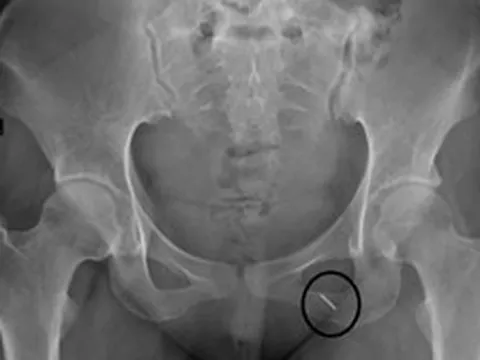

Thủ kim phòng "thượng mã phong" đêm tân hôn, cô gái bị kim chui vào người

() - Cô gái 23 tuổi ở Hưng Yên được đưa đến viện trong tình trạng đau buốt khi vận động mạnh, nghi kim khâu chui vào người. Ở bệnh viện tuyến dưới, bác sĩ đã chích da nhưng không tìm thấy dị vật.